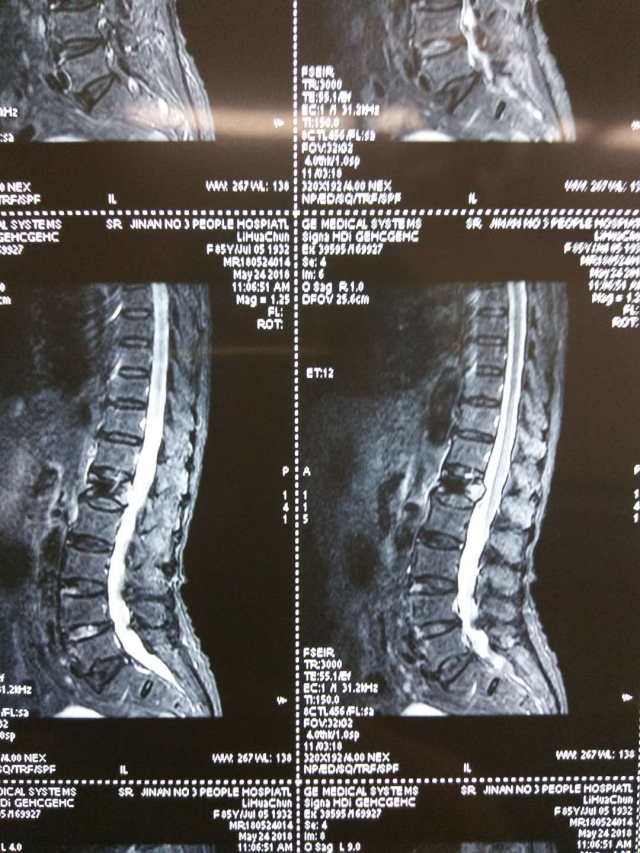

老人前几日突然感到腰部疼痛,起立及翻身活动时加重,平躺休息时疼痛才稍稍减轻,在家吃了几天药,但不见什么效果,而且疼痛逐渐加重,在市三院经过腰椎核磁扫描后,显示为「腰 1 椎体压缩骨折」,结合老人的身体状况,医生推测很可能因为骨质疏松引起了骨折。

经过患者家属同意后,脊柱外科为其实施了「经皮椎体后凸成形术」,术后患者恢复良好。